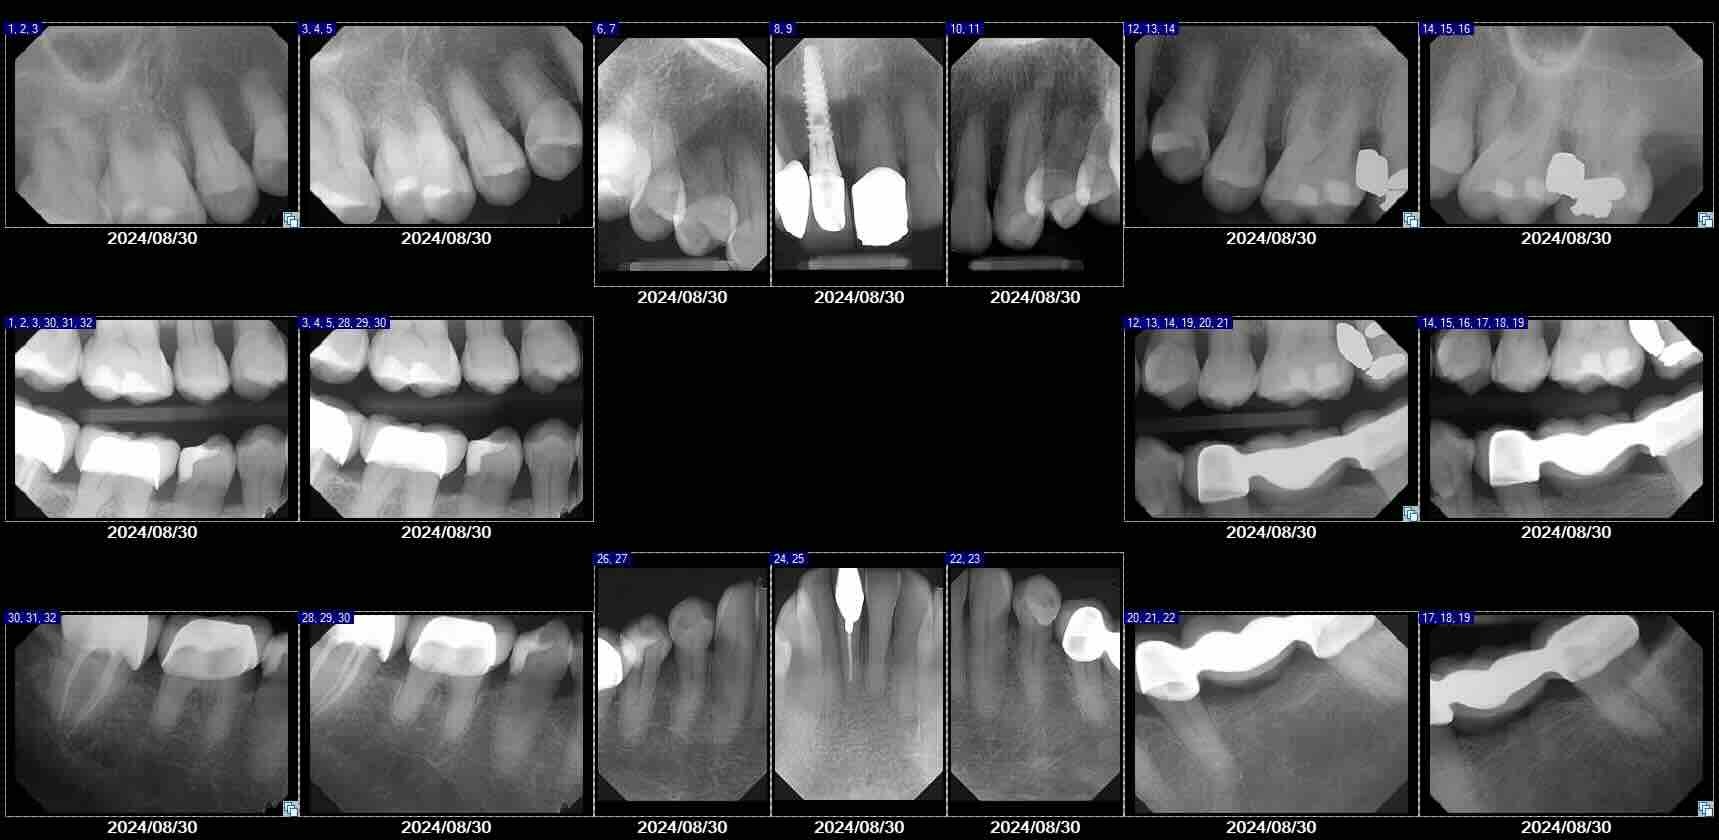

Digital dental X-rays use low-radiation technology to capture clear images of your teeth, roots, and jaw. They help detect issues that are not visible during a regular exam, such as cavities between teeth, infections, bone loss, and the position of unerupted teeth. Digital X-rays are fast, safe, and essential for accurate diagnosis.

Digital dental X-rays allow your dentist to see areas that are not visible during a regular exam. Depending on your needs, different types of X-rays may be used. Bitewing X-rays help detect cavities between teeth, while periapical X-rays show the entire tooth, including the root and surrounding bone. A full-mouth series (FMX) is often recommended for new patients to provide a complete overview of oral health. Panoramic X-rays capture the entire jaw, sinuses, and bone structure in a single image, and in more complex cases, a CBCT scan may be used to create detailed 3D images for implant planning or advanced treatment.